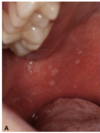

What are these radiographic findings?

Residual Cysts

What is the radiographic finding?

Residual Cyst